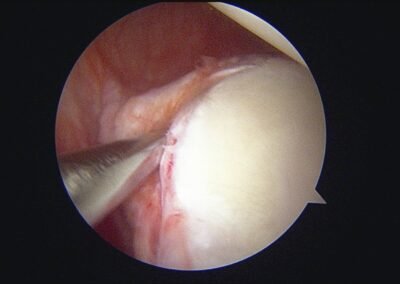

GalleryShoulder rotator cuff repair Meniscus root repair Meniscus repair Bankart repair for recurrent shoulder dislocation ACL reconstruction Machines Instruments